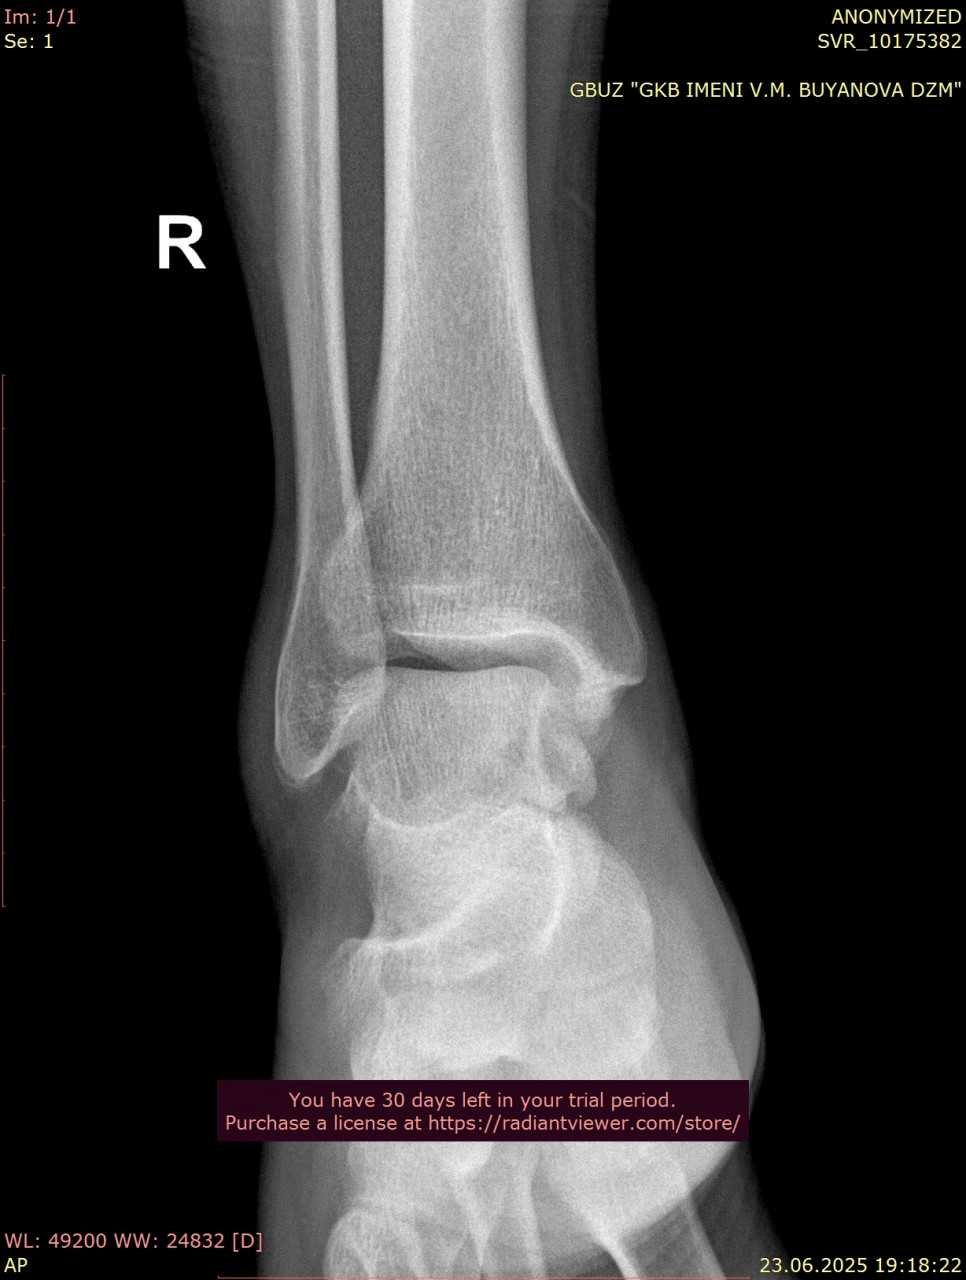

Посмотрите, пожалуйста, еще раз снимки голеностопного сустава, от 23.06.2025, когда был перелом (прикрепляю только 1 проекцию из за лимита файлов на сайте) и от 25.08.2025. Нет ли избыточного разрастания костей в области внутренней лодыжки? Если есть, то какие могут быть последствия? На сегодняшний день боли и ограничения подвижности пока нет. Заранее спасибо!

Здравствуйте. По контрольным снимкам от 25.08 выраженного избыточного костного разрастания в области внутренней лодыжки не видно и отмечается формирование нормального костного мозоля. Если в дальнейшем появятся боли или ограничение движений это может указывать на избыточное разрастание, но сейчас сустав выглядит благополучно. Рекомендую продолжать наблюдение и выполнять ЛФК.